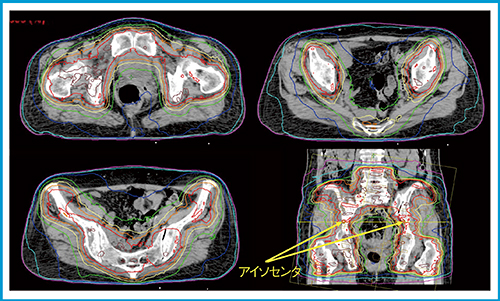

全脳全脊髄照射のように頭尾方向に長いターゲットに対しては,頭尾方向にビームをオーバーラップさせて線量分布を作成するが,全骨盤のように左右方向に大きなターゲットには,左右方向に照射野をオーバーラップさせて線量最適化を行う。図5に,骨盤に対する2アイソセンタRapidArcの治療計画例を示す。

図5 骨盤2アイソセンタRapidArcの治療計画例